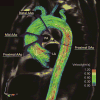

Results: All patients with right-left bicuspid aortic valve exhibited peak wall shear stress at the right-anterior position of the ascending aorta (bicuspid aortic valve vs trileaflet aortic valve at the right-anterior position: 0.91 ± 0.23 N/m2 vs 0.43 ± 0.12 N/m2, P < .001) with no distinct alteration between bicuspid aortic valve with severe aortic insufficiency and bicuspid aortic valve with severe aortic stenosis. The predominance of dilatation involving the tubular ascending aorta (82%, type 2 aortopathy) persisted, with or without valve dysfunction. Compared with bicuspid aortic valve control subjects, the bicuspid aortic valve with severe aortic insufficiency group displayed universally elevated wall shear stress (0.75 ± 0.12 N/m2 vs 0.57 ± 0.09 N/m2, P < .01) in the ascending aorta, which was associated with elevated cardiac stroke volume (P < .05). The bicuspid aortic valve with severe aortic stenosis group showed elevated flow eccentricity in the form of significantly increased standard deviation of circumferential wall shear stress, which correlated with markedly increased peak aortic valve velocity (P < .01).

Conclusions: The location of peak aortic wall shear stress and type of aortopathy remained homogeneous among patients with right-left bicuspid aortic valve irrespective of valve dysfunction. Severe aortic insufficiency or stenosis resulted in further elevated aortic wall shear stress and exaggerated flow eccentricity.